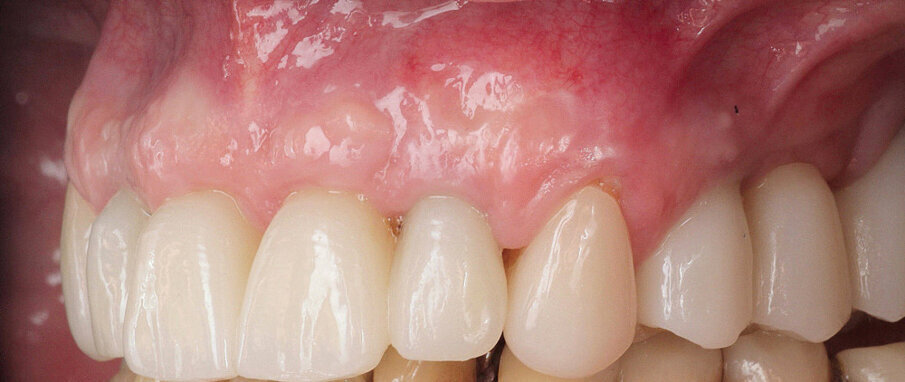

Slika 1: Početna situacija kod pacijenta – ekstraoralno.

58-godišnjakinja, nepušačica i sistemski zdrav pacijent kojeg je njen doktor dentalne medicine uputio u naš centar radi implanto-protetske terapije. Pacijenticu je uglavnom smetala loša estetika u gornjem frontalnom području, koje je karakterizirala visoka linija osmijeha i izražene anomalije položaja zuba (Slike 1. i 2.), kao i funkcionalna ograničenja kao posljedica neugode prilikom žvakanja. Tri zuba su nedostajala u gornjoj distalnoj regiji i to zubi 17, 15 i 27 koji nisu bili protetski opskrbljeni, dok je u donjoj čeljusti u distalnoj regiji nedostajalo pet zuba s obje strane u području premolara te su oni zamijenjeni djelomičnom mobilnom protezom. Svi preostali zubi u gornjoj i donjoj čeljusti bili su prema klasifikaciji „Proceedings of the World Workshop on the Classification of Periodontal and Peri-implant Diseases and Conditions 2017“ imali parodontitis stadija IV, a prosječna dubina sondiranja parodonta je bila 5,6 mm. 7 Prosječni indeks krvarenja (BOP) i srednji indeks plaka (PI) bili su 70 odnosno 80 posto. S obzirom na paradontološke parametre i mjere oralne higijene (vidljivi kamenac i naslage), oralna higijena pacijentice klasificirana je kao loša. Pacijentica je u drugoj ordinaciji liječena s dva implantata u desnoj maksilarnoj stražnjoj regiji kako bi se zamijenili prvi pretkutnjak i prvi kutnjak (Slika 3). Prema definiciji koju je Weißgold uveo 1977. godine, pacijent ima debeli biotip. 26

Slika 15.

Slika 16.

Slika 17.

Slika 18.

Slika19.

Slika 20.

Slika 14. Frontalni prikaz definitivne protetske nadogradnje. Odnosi pokazuju dobru estetiku bez znakova komplikacija mekih tkiva Slika 15. Pogled na definitivni rad s desne strane. Slika 16. Pogled na definitivni rad s lijeve strane. Slika 17. Završna rendgenska slika s definitivnim implanto protetskim radom in situ. Slika 18. Frontalni prikaz definitivnog protetskog rada nakon dvogodišnjeg praćenja. Slika 19. Prikaz definitivnog protetskog rada s lijeve strane nakon dvogodišnjeg praćenja. Slika 20. Prikaz definitivnog protetskog rada s desne strane nakon dvogodišnjeg praćenja.